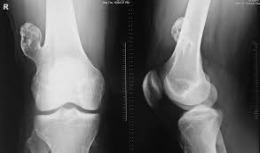

• Οστεοειδές οστέωμα, καλοήθης όγκος,  ο οποίος προκαλεί συνήθως πόνο κατά τη διάρκεια της νύχτας. Συνήθως  θεραπεύεται με καυτηριασμό με ραδιοσυχνότητες.

Η ακτινογραφία απεικονίζει ένα οστεοειδές οστέωμα  στο άνω μέρος του μηριαίου, το οποίο θεραπεύτηκε από τον Δρ. Ζένιο, με την χρήση καυτηριασμού με ραδιοσυχνότητες.